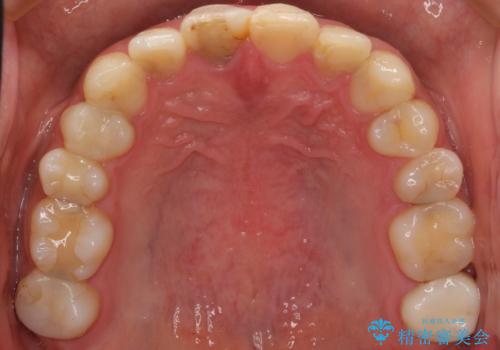

憧れの芸能人のような白い歯に 30代男性

- 憧れの芸能人(ヴィジュアル系バンドマン)のような歯になりたいとのご希望で来院された患者様です。

咬み合わせが悪く矯正も検討されていたそうですが、歯を真っ白にしたいというご希望もあり、28本のすべての歯をセラミックにしたいとのことでした。

精査したところ、ほとんどの歯が保険内のレジンで充填されており、咬み合わせも悪く咬合していない歯もありました。

虫歯をしっかりと治療したのち、オールセラミッククラウンによる補綴治療を行いました。

憧れのヴィジュアル系バンドマンのような白い歯になり、喜んで下さいました。

不適なレジン充填によるデコボコがなくなったことで歯磨きしやすくなり、また気にされていた咬み合わせも良くなり、ご満足頂けました。

クラウンの種類:オールセラミッククラウン スタンダード

シェード:NW0